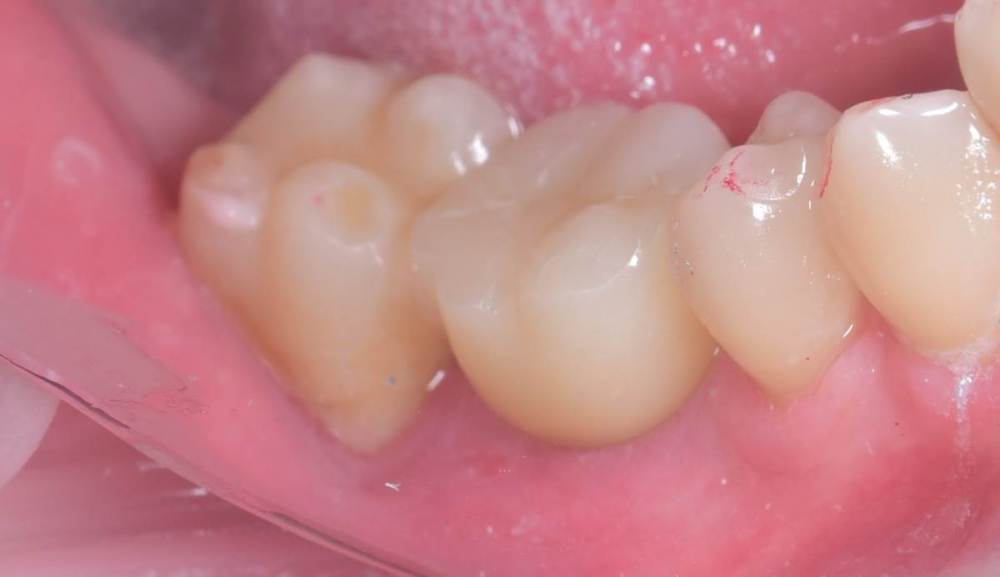

TIGER Опубликовано 14 июля, 2023 Автор Поделиться Опубликовано 14 июля, 2023 всем привет!Не всегда одномоментная имплантация метод выбора,в данном кейсе пошёл по более прогнозируемому пути для сохранения тканей 1 1 Ссылка на комментарий

Doc Опубликовано 14 июля, 2023 Поделиться Опубликовано 14 июля, 2023 7 часов назад, TIGER сказал: всем привет!Не всегда одномоментная имплантация метод выбора,в данном кейсе пошёл по более прогнозируемому пути для сохранения тканей И очень неплохо получилось 1 1 Ссылка на комментарий

TIGER Опубликовано 15 июля, 2023 Автор Поделиться Опубликовано 15 июля, 2023 @Irouil было бы сложно стабилизировать в этих условиях,в случае неуда ситуация усугблялась,решил пойти по пути сохранения тканей,дал организму самому регенирировать,при имплантации добавил чуть тканей @Doc ещё Миш писал в книге о минусах имплантации семёрок кстати 1 Ссылка на комментарий